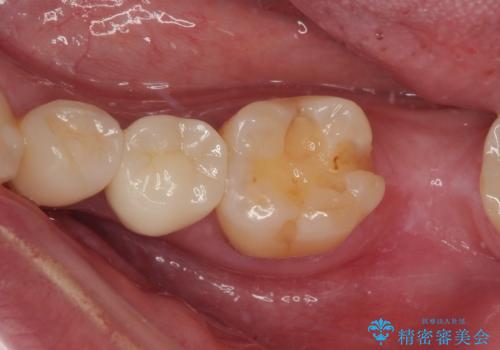

詰め物が外れかけてるのでやり替えたい セラミックインレー修復・フルジルコニアクラウン